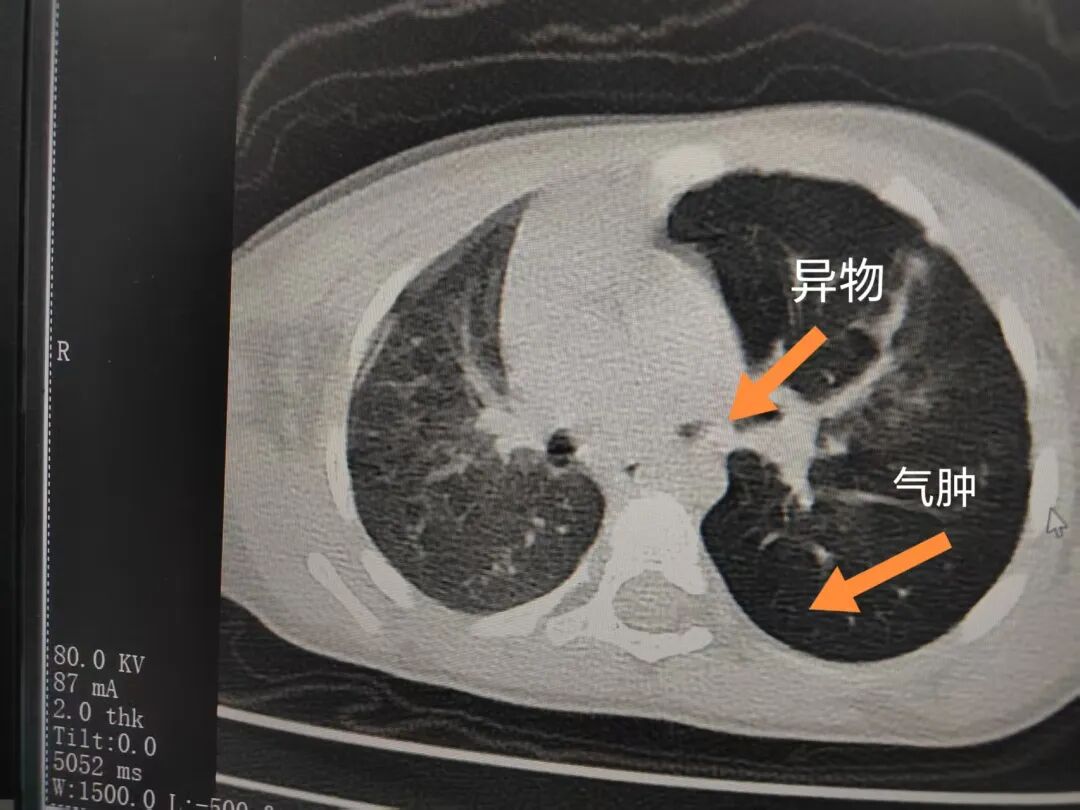

三天后(11月13日),趙寶出現(xiàn)高熱、咳喘加重,家長著急了,再次帶他來到醫(yī)院。CT檢查顯示左肺過度充氣,左肺上下葉支氣管主干見不規(guī)則高密度影,左肺上葉可見大片狀密度增高影,縱隔窗實(shí)變,提示為“左側(cè)支氣管內(nèi)異物并繼發(fā)性改變,左肺上葉舌段肺膨脹不全”。

市二院小兒呼吸內(nèi)科副主任楊亞娟介紹,異物誤入氣道可能導(dǎo)致氣道阻塞,嚴(yán)重時(shí)可引發(fā)窒息,甚至危及生命。若異物進(jìn)入支氣管,造成不完全堵塞,可引起阻塞性肺氣腫;如完全堵塞支氣管,則可能導(dǎo)致肺組織萎縮,形成肺不張。此外,若異物存留時(shí)間較長,或?yàn)橹参镄援愇铮菀缀喜⒓?xì)菌感染,產(chǎn)生膿性分泌物,進(jìn)而發(fā)展為肺炎。她強(qiáng)調(diào),盡早診斷并取出異物,是減少并發(fā)癥、降低病死率的關(guān)鍵。